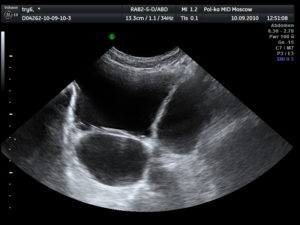

В норме мочевой пузырь визуализируется как образование правильной овоидной формы, нормальных размеров, с четкими ровными контурами и анэхогенным однородным содержимым. ООМ не должен превышать 50 мл.

При цистите внутренние контуры мочевого пузыря становятся неровными, в просвете органа видны хлопья и конгломераты – частицы слущенного эпителия, скопления микробов, песок, сгустки гноя или крови.

Для язвенной формы цистита характерны дефекты слизистой в виде углублений – эрозий.

Воспаленные стенки обычно утолщены, а сам пузырь при остром заболевании увеличивается в размерах, а при хроническом может уменьшаться.